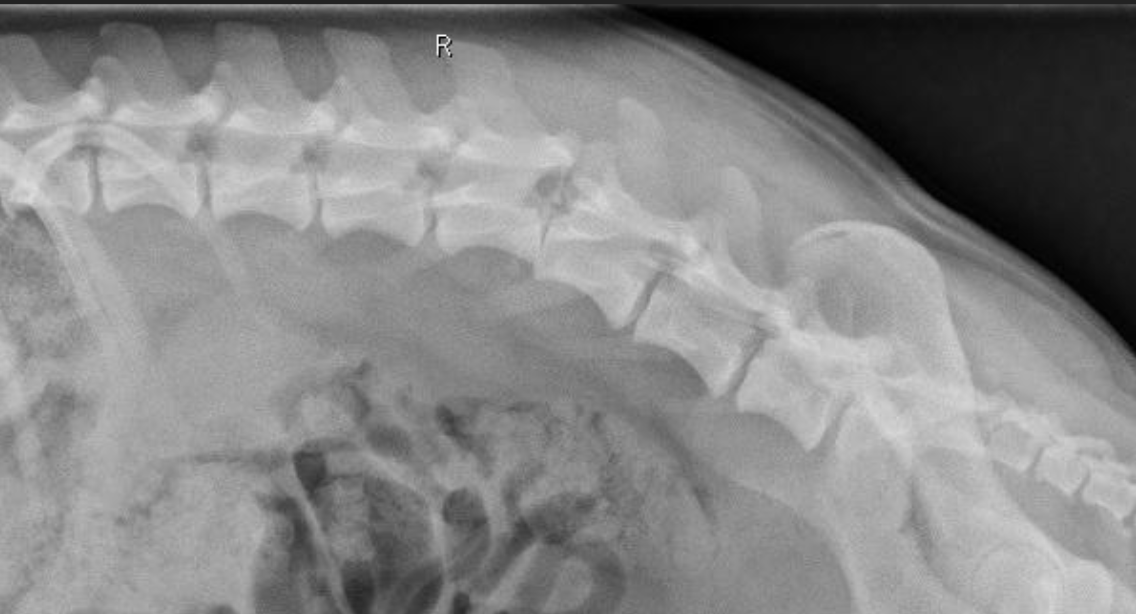

What are the characteristics of radiographs as a diagnostic for spinal trauma?

A

-thoracic rads, survey rads, and spinal rads typically performed

-lateral views okay to perform

-VD view should be taken with horizontal beam; do NOT place patient on back

-fairly good sensitivity at recognizing subluxations and fractures

-okay sensitivity at detecting fragments in spinal canal (compared to CT)

-avoid sedation if possible; can cause relaxation and instability of fractures